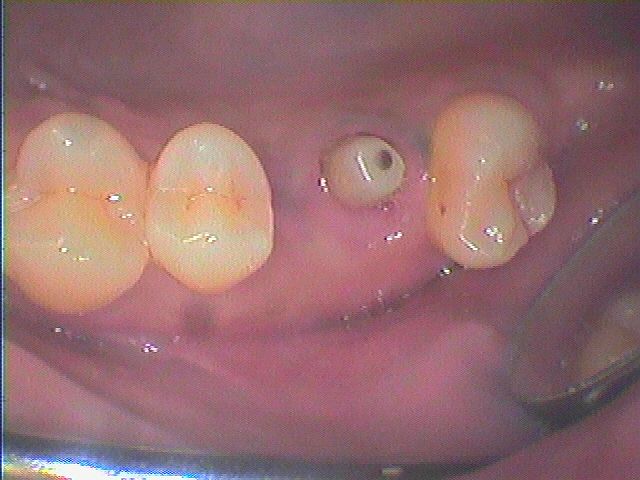

右上の奥から2番目の歯を何とかしてほしい 他医院にて口蓋根のみ残して被せたけど嚙むと痛くて入れれない インプラント治療の臨床現場